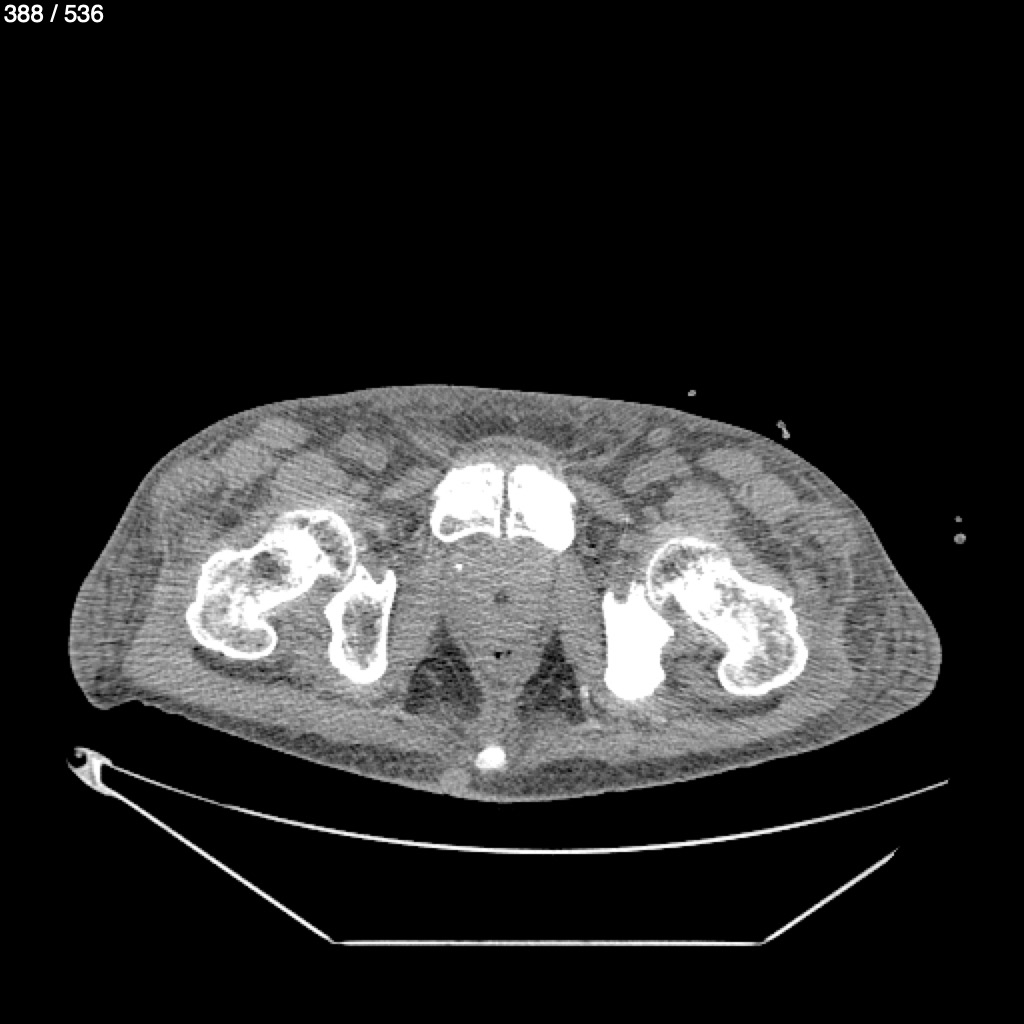

Angel Villalobos Palomeque 73 A - T.C Abdomen Simple